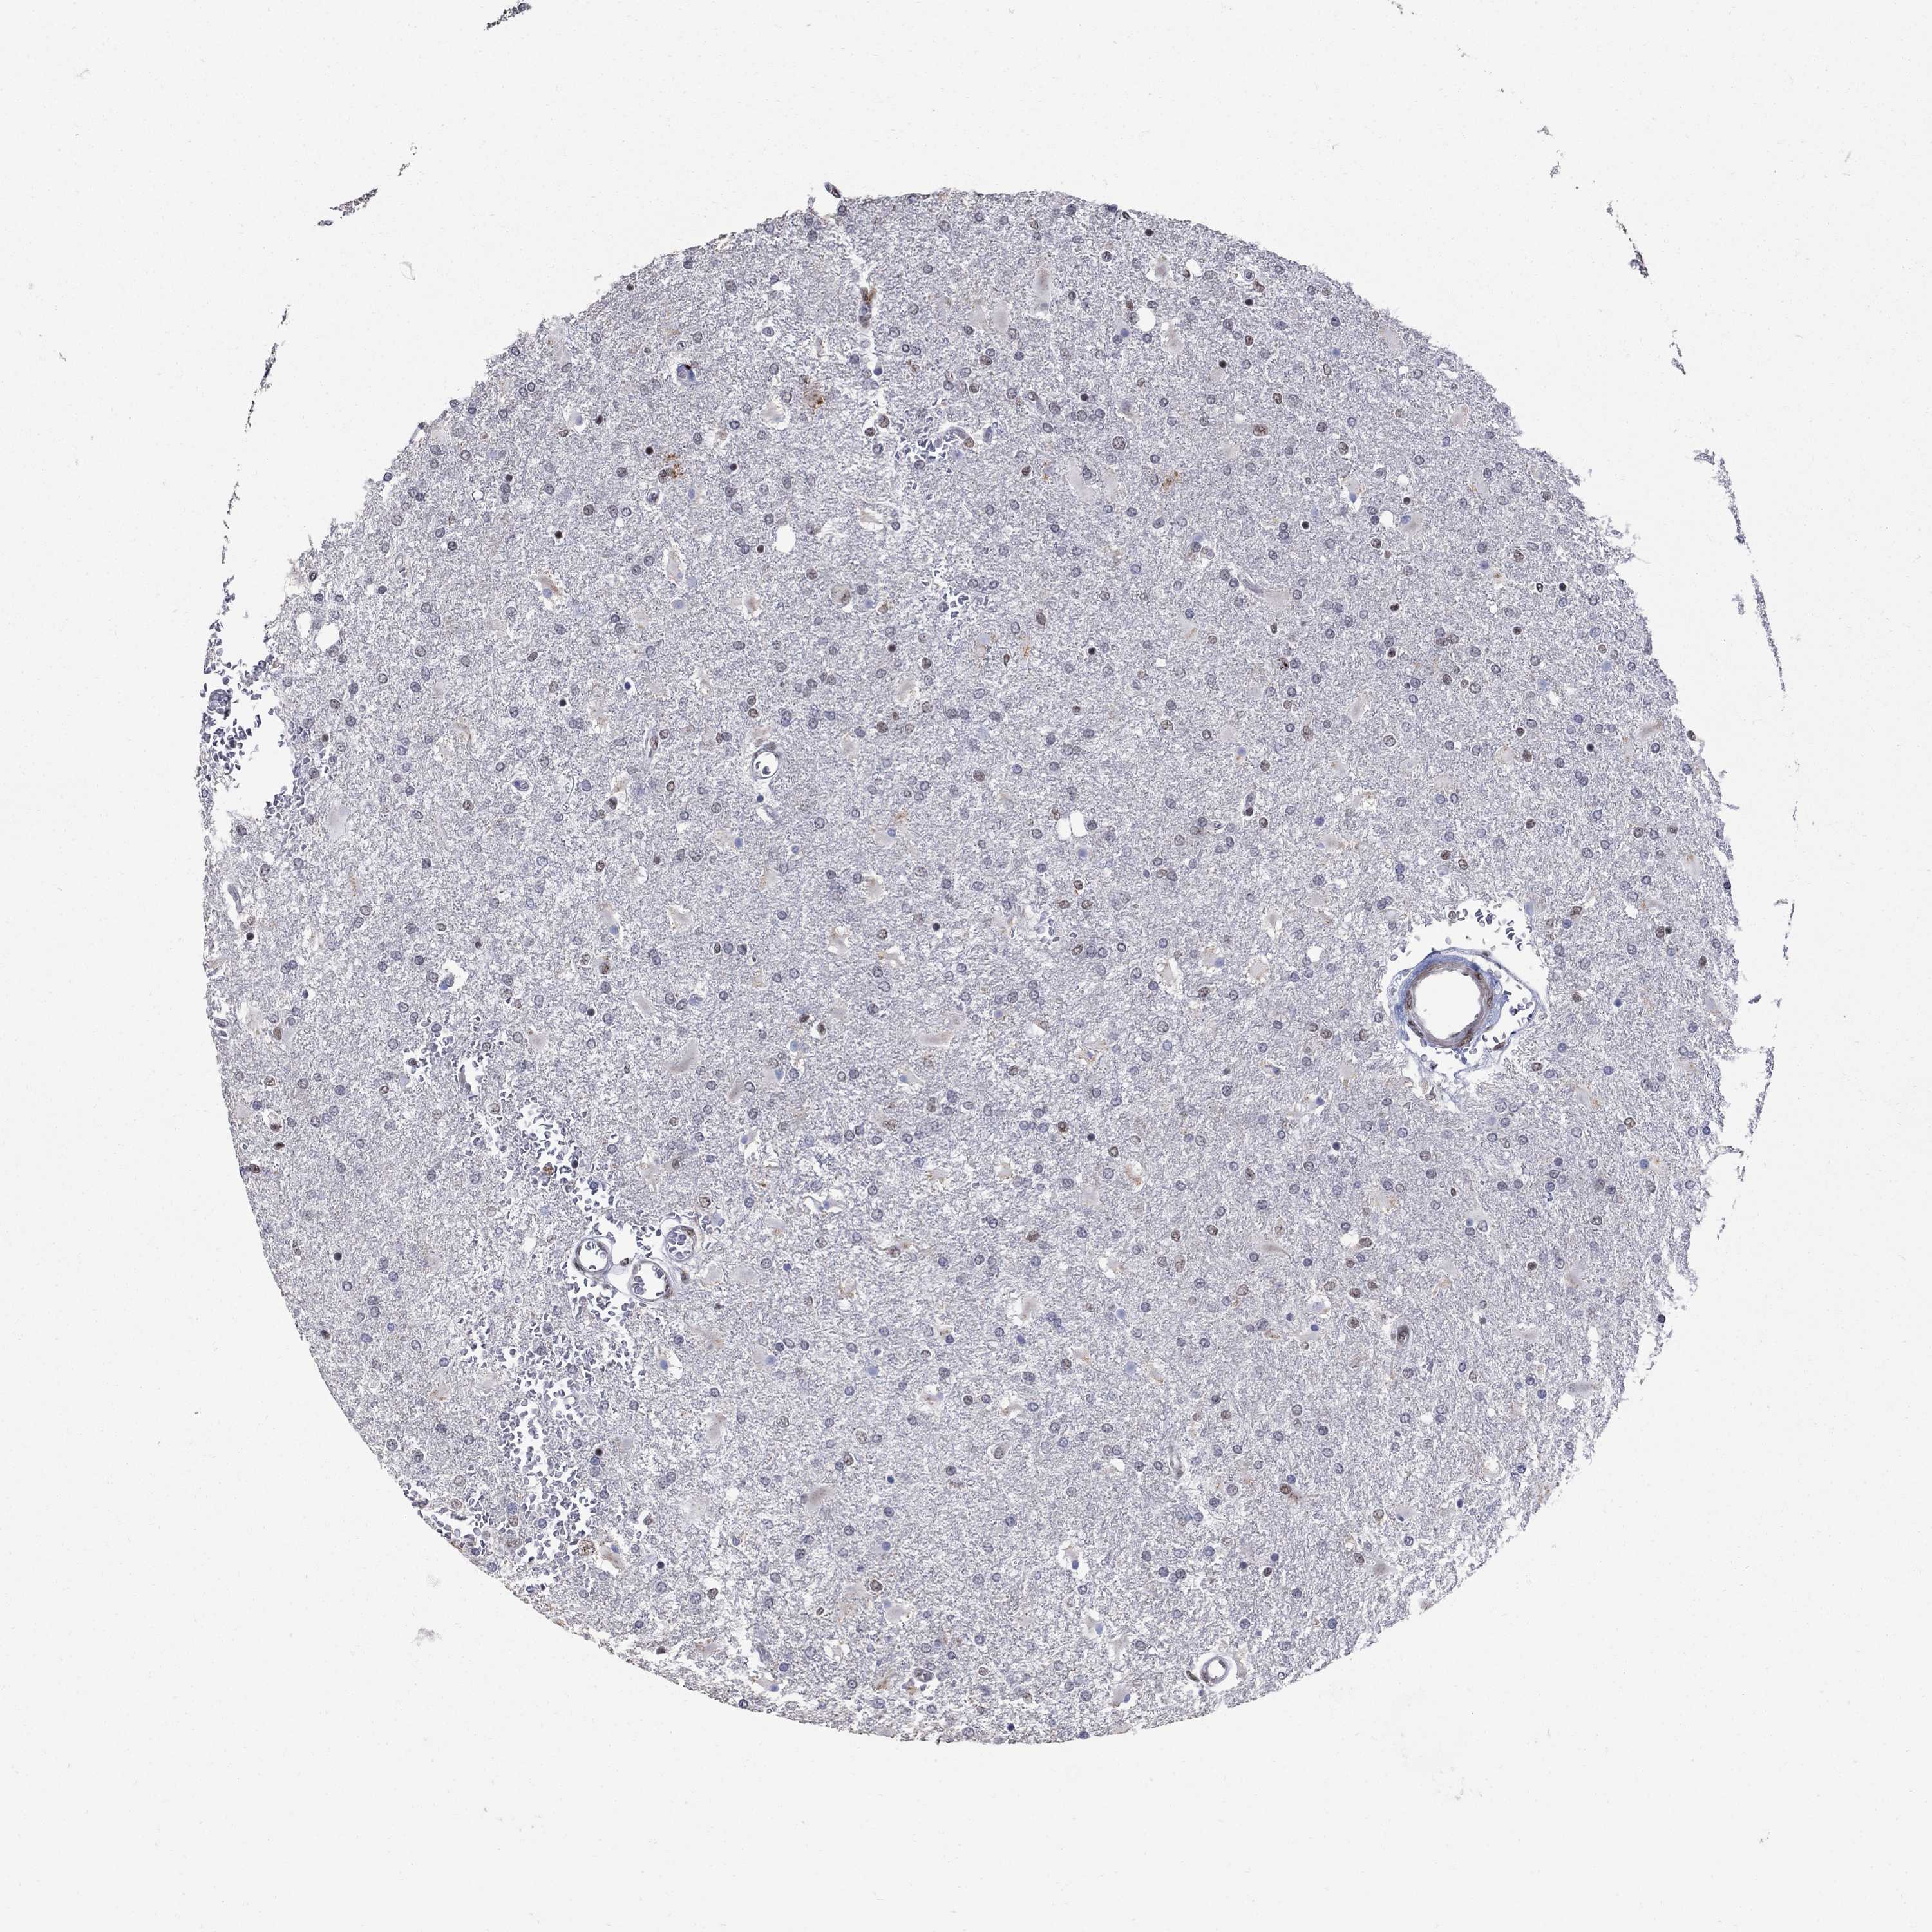

GLIOMA - Protein expressioni

A mouse-over function shows sample information and annotation data. Click on an image to view it in a full screen mode. Samples can be filtered based on level of antibody staining by selecting one or several of the following categories: high, medium, low and not detected. The assay and annotation is described here.

Note that samples used for immunohistochemistry by the Human Protein Atlas do not correspond to samples in the TCGA dataset.

Antibody stainingi

Antibody staining in the annotated cell types in the current human tissue is reported as not detected, low, medium, or high, based on conventional immunohistochemistry profiling in selected tissues. This score is based on the combination of the staining intensity and fraction of stained cells.

Each image is clickable and will lead to virtual microscopy that enables deeper exploration of all samples and also displays staining intensity scores, fraction scores and subcellular localization as well as patient and tissue information for each sample.

Antibody HPA075076

Staining

High

Medium

Low

Not detected

Intensity

Strong

Moderate

Weak

Negative

Quantity

>75%

75%-25%

<25%

None

Location

Nuclear

Cytoplasmic/membranous

Cytoplasmic/membranous,nuclear

Glioma, malignant, Low grade

Glioma, malignant, High grade

Glioma, malignant, NOS